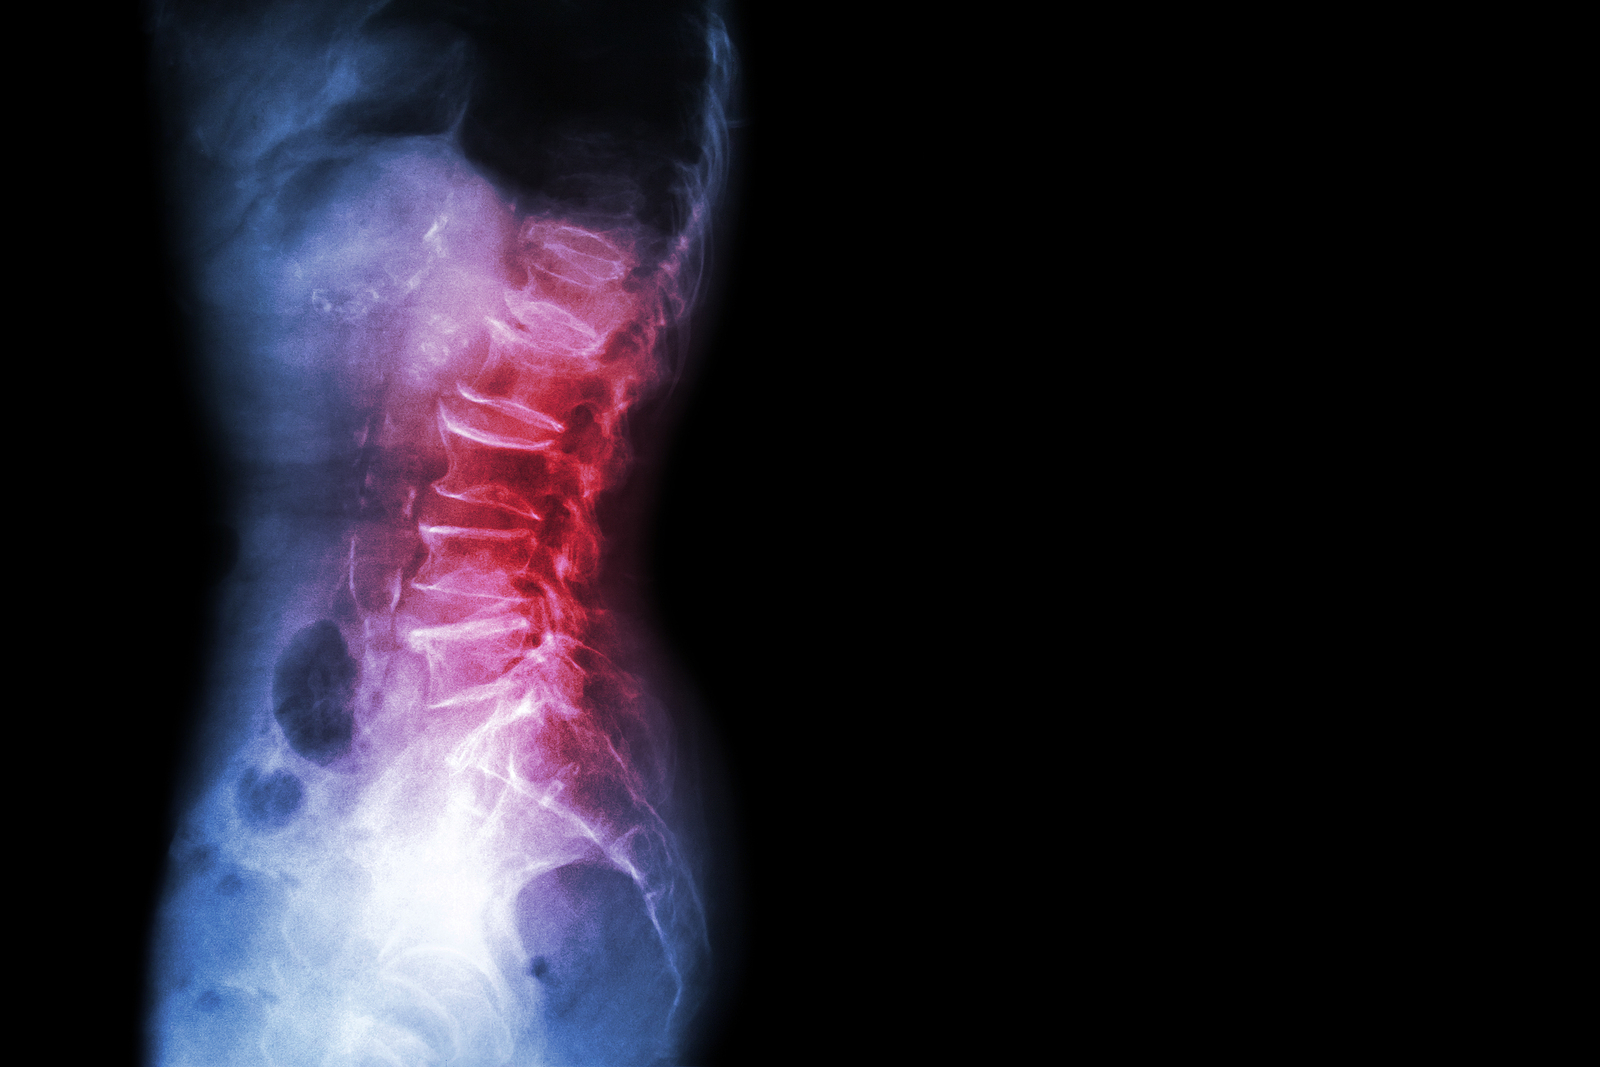

The human spine is made up of 24 spinal bones, called vertebrae, as well as the sacrum and the coccyx. The sacrum is a triangular bone near the bottom of the spine and the coccyx is more commonly known as the tailbone.

Vertebrae are stacked on top of one another to create the spinal column. The spinal column gives the body its form and helps sustain an upright position.

The lumbar spine—where pain is often experienced—is made up of five vertebrae positioned near the bottom of the spinal column. Doctors often refer to these vertebrae as levels L1, L2, L3, L4 and L5. The ‘L’ refers to ‘lumbar’. The lowest vertebra, L5, is connected to the top of the sacrum—a triangular bone at the base of the spine that is located between the two pelvic bones. Some people are born with an extra or sixth lumbar vertebra called L6. Having an extra vertebra doesn't usually cause physical problems.

X-rays are usually the first test ordered before any of the more specialized tests are completed. X-rays use electromagnetic radiation to show problems with bones and can also reveal problems such as fractures, infections, or bone tumors. X-rays of the spine can give your doctor information about bone alignment and can demonstrate how much degeneration has occurred in the spine. Both alignment and degeneration can affect the amount of space in the neural foramina and between the discs, which subsequently impacts the nerves in the area. This is important information your health care professional can use to establish a treatment plan.